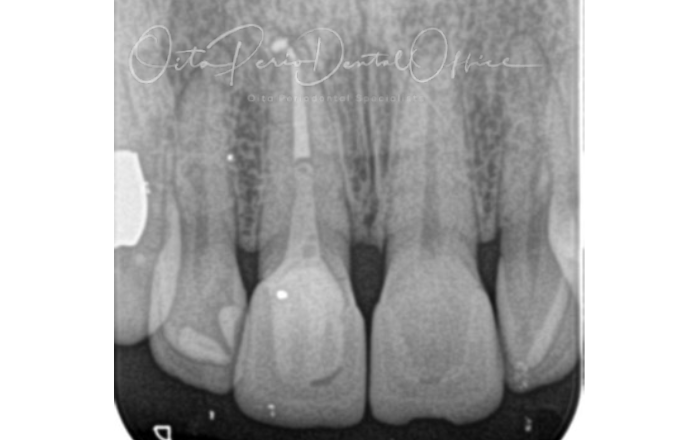

治療前のレントゲン